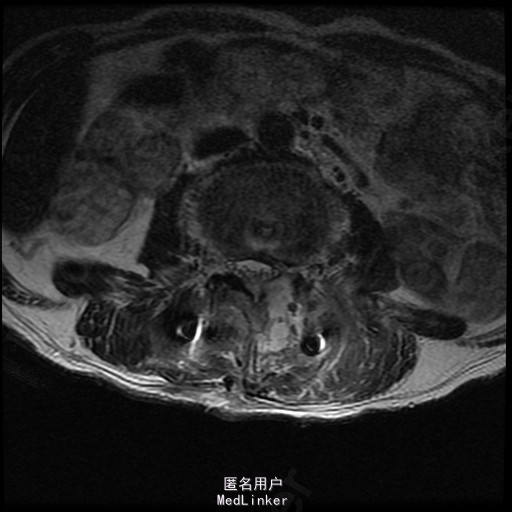

查体:左侧小腿外侧、足背感觉减退,右侧正常,双侧屈髋、伸膝、踝背伸肌肌力5级,左侧踇背伸、跖屈肌肌力4级,右侧踇背伸、跖屈肌肌力4-5级,双侧巴氏征阴性,直腿抬高试验左侧30°阳性,右侧阴性。 辅助检查: X-ray:腰椎退行性变,腰椎节段性性不稳 MR:腰椎间盘突出,腰3/4,4/5,腰4/5节段明显

随访 术后患者下肢麻木感觉较前好转,左侧踝背伸、跖屈肌力4级+,左侧肢体抬高试验阴性。术后MR检查减压彻底 讨论:1、腰椎椎管狭窄手术指证的把握,腰椎后路手术,腰椎椎间融合与椎板减压的选择? 2、术中探查如无明显间盘突出,以椎管骨性狭窄为主,可行腰椎后路椎板减压为主。